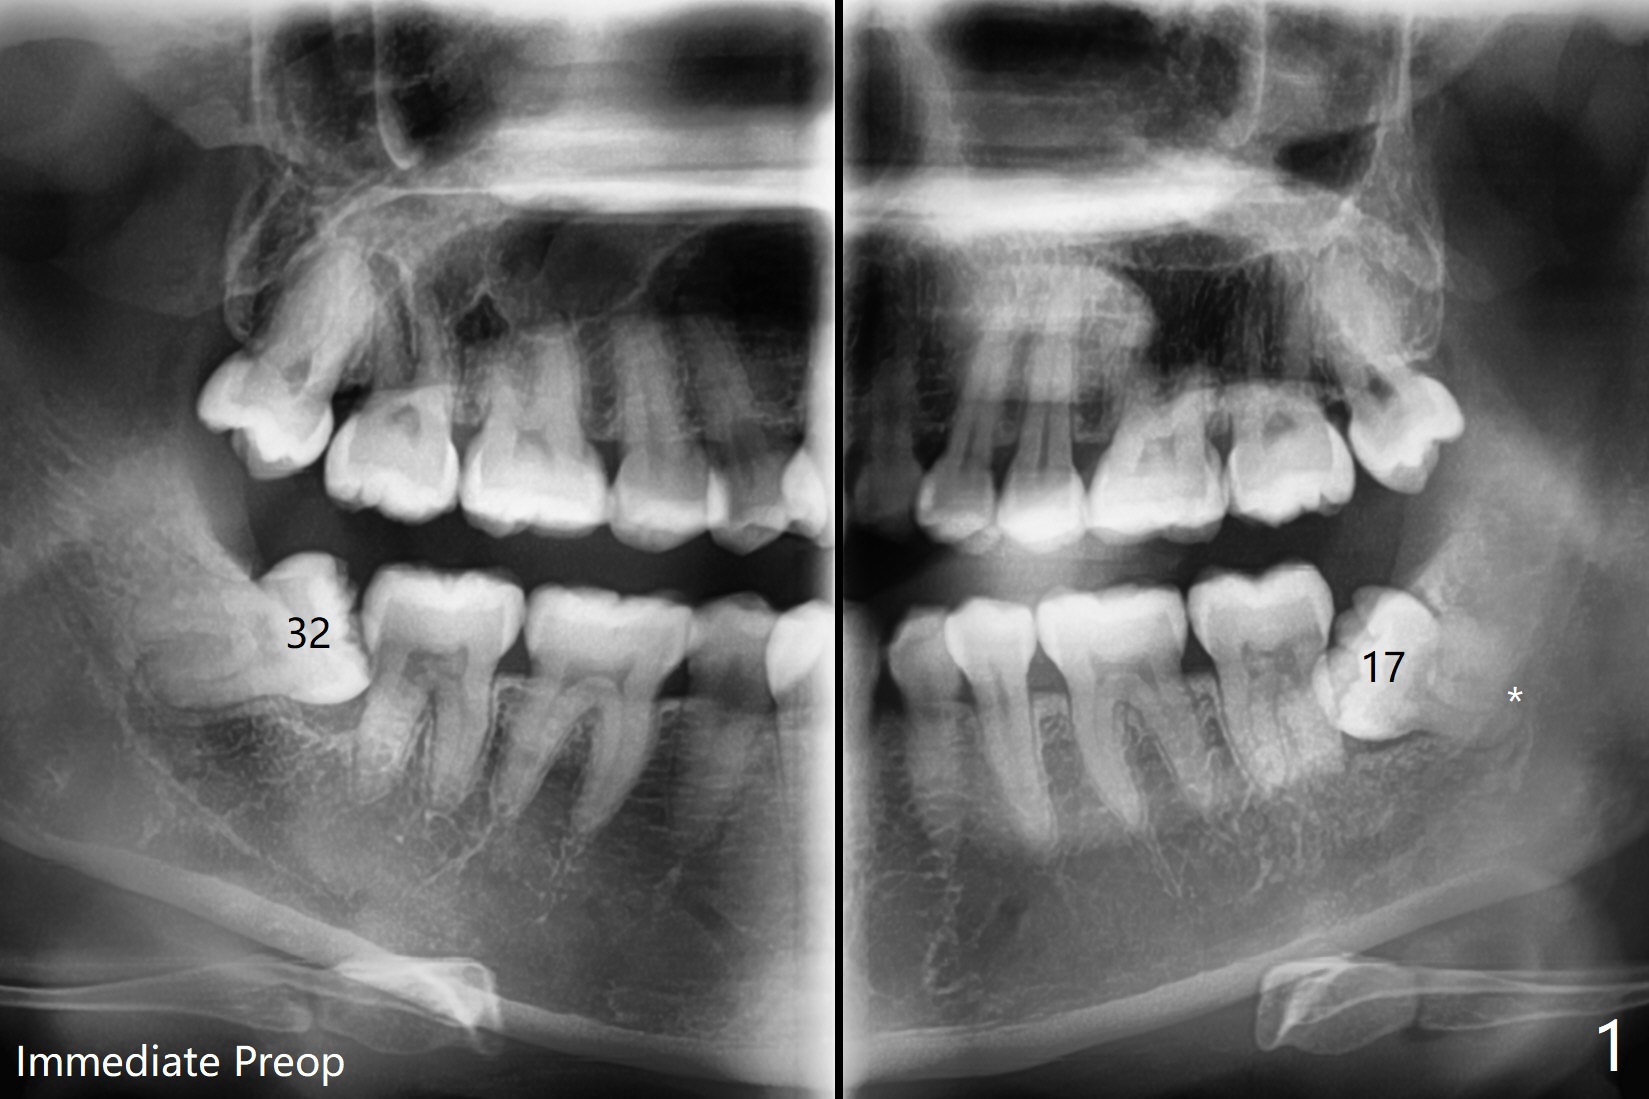

A 35-year-old timid woman finally decides to have 4 of the 3rd molars extracted (Fig.1). The apices of #17 overlaps with the Inferior Alveolar Canal (*). Small field CT shows that #17 is buccal to #18 (Fig.2), causing distal root exposure (Fig.3 D). In fact the buccal overlap seems to be more severe clinically (Fig.4) than what X-ray indicate (Fig.1,3). Therefore bone graft seems to be able to be packed mesially (Fig.5: G). In fact the left Inferior Alveolar Canal is exposed after extraction, collagen plug (P) is placed distal without use of curette around the exposed canal.